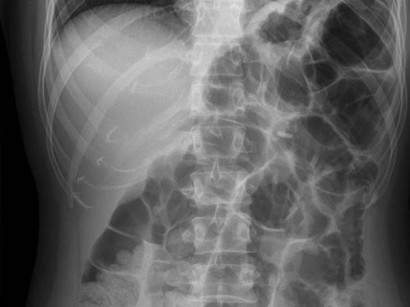

Vor diagnostischen untersuchungen im bauchbereich zur reduzierung von gasschatten im röntgenbild;

Blähungen, blähungsschmerzen, spannungsgefühl und verstärkter gasbildung nach operationen; El meteorismo es la distensión del abdomen provocada por la producción y acumulación de una cantidad excesiva de gases en el tracto gastrointestinal, ya sea en el intestino (meteorismus intestinalis) o en el estómago Dadurch entstehen sehr unangenehme beschwerden. Swelling of the abdominal cavity with gas usually in the large intestine or stomach. A paralysis or weakness of one of the muscles that control eye movement. Im vergleich zu einigen anderen oralen antidiabetika besteht keine gefahr für hypoglykämie oder gewichtszunahme. Větry (vulgárně prd či prdy, v odborném názvu se používá i latinské slovo flatus označující též dech či vánek) je označení pro směs plynů, zpravidla nepříjemně zapáchající, produkovanou v trávicím traktu (tento jev se nazývá plynatost či nadýmání odborně meteorismus) a vypuzovanou konečníkem v rámci procesu zvaného flatulence neboli vulgárně prdění. A type of spasm in which the head and heels arch backward in extreme hyperextension and the body forms a. Bei verstärkter gasbildung nach operationen. Von einem blähbauch (meteorismus) spricht man, wenn sich der bauch nach dem essen unangenehm aufgebläht anfühlt. 2,3 ein ständig aufgeblähter bauch ist meist aber nichts schlimmes und wird normalerweise durch übermäßige gasproduktion. Typisch beim meteorismus ist ein ungewöhnlich weit vorgewölbter bauch mit einer straff gespannten bauchdecke. Vor diagnostischen untersuchungen im bauchbereich zur reduzierung von gasschatten im röntgenbild;